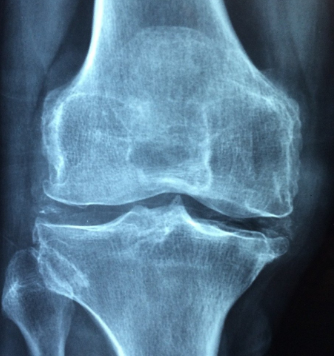

무릎 앞쪽에서 발생하는 통증으로는 슬개대퇴증후군, 슬개건염, 연골연화증과 같은 것들이 대표적인 원인 입니다. 무릎 앞쪽의 구조는 무릎의 뼈중 뚜껑뼈인 슬개골을 중심으로 상부에는 대퇴사두근건과 아래쪽으로는 슬개건이라고하는 힘줄 부분이 있습니다. 또한 무릎관절과 양쪽 골반 사이 부분에 위치해 허벅지를 지탱해 주는 넙다리뼈라고 불리는 대퇴골이 자리하고 있습니다.

무릎 연골연화증은 무릎뼈를 감싸고 있는 연골이 부드러워지거나 약해지면서 탄력을 잃고 충격을 이기지 못하고 손상되는 질환을 말합니다. 초기 당시에는 단순한 염증으로 시작되는 질환이지만 점차 연골 전체 부분에 균열로 이어져 뒤 손상 단계로 진행돼 무릎의 기능을 떨어뜨리게 됩니다.